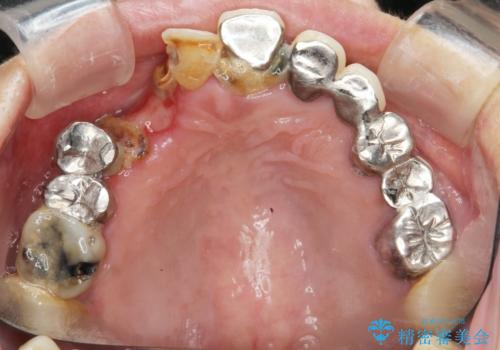

痛くて噛めない インプラントで全て治療したい

- 痛くて噛めない、これまでだましだまし治療をしてきたがこれを機にすべてきっちりと治したい、口の中の悩みを解決したいと来院されました。

抜歯や歯周病治療、欠損補綴を含め、全顎的な治療を計画・提案します。

口腔内に歯の破折や歯周病、虫歯、欠損など複数の問題が存在する場合局所的に問題を解決していくのではなく全顎的な治療を行っていくことで長期的な予後を見込むことができます。